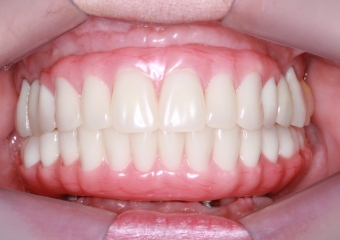

Próteses fixas definitivas em resina em Outubro de 2016 - Clínica Cliniface

Próteses fixas definitivas em resina em Outubro de 2016